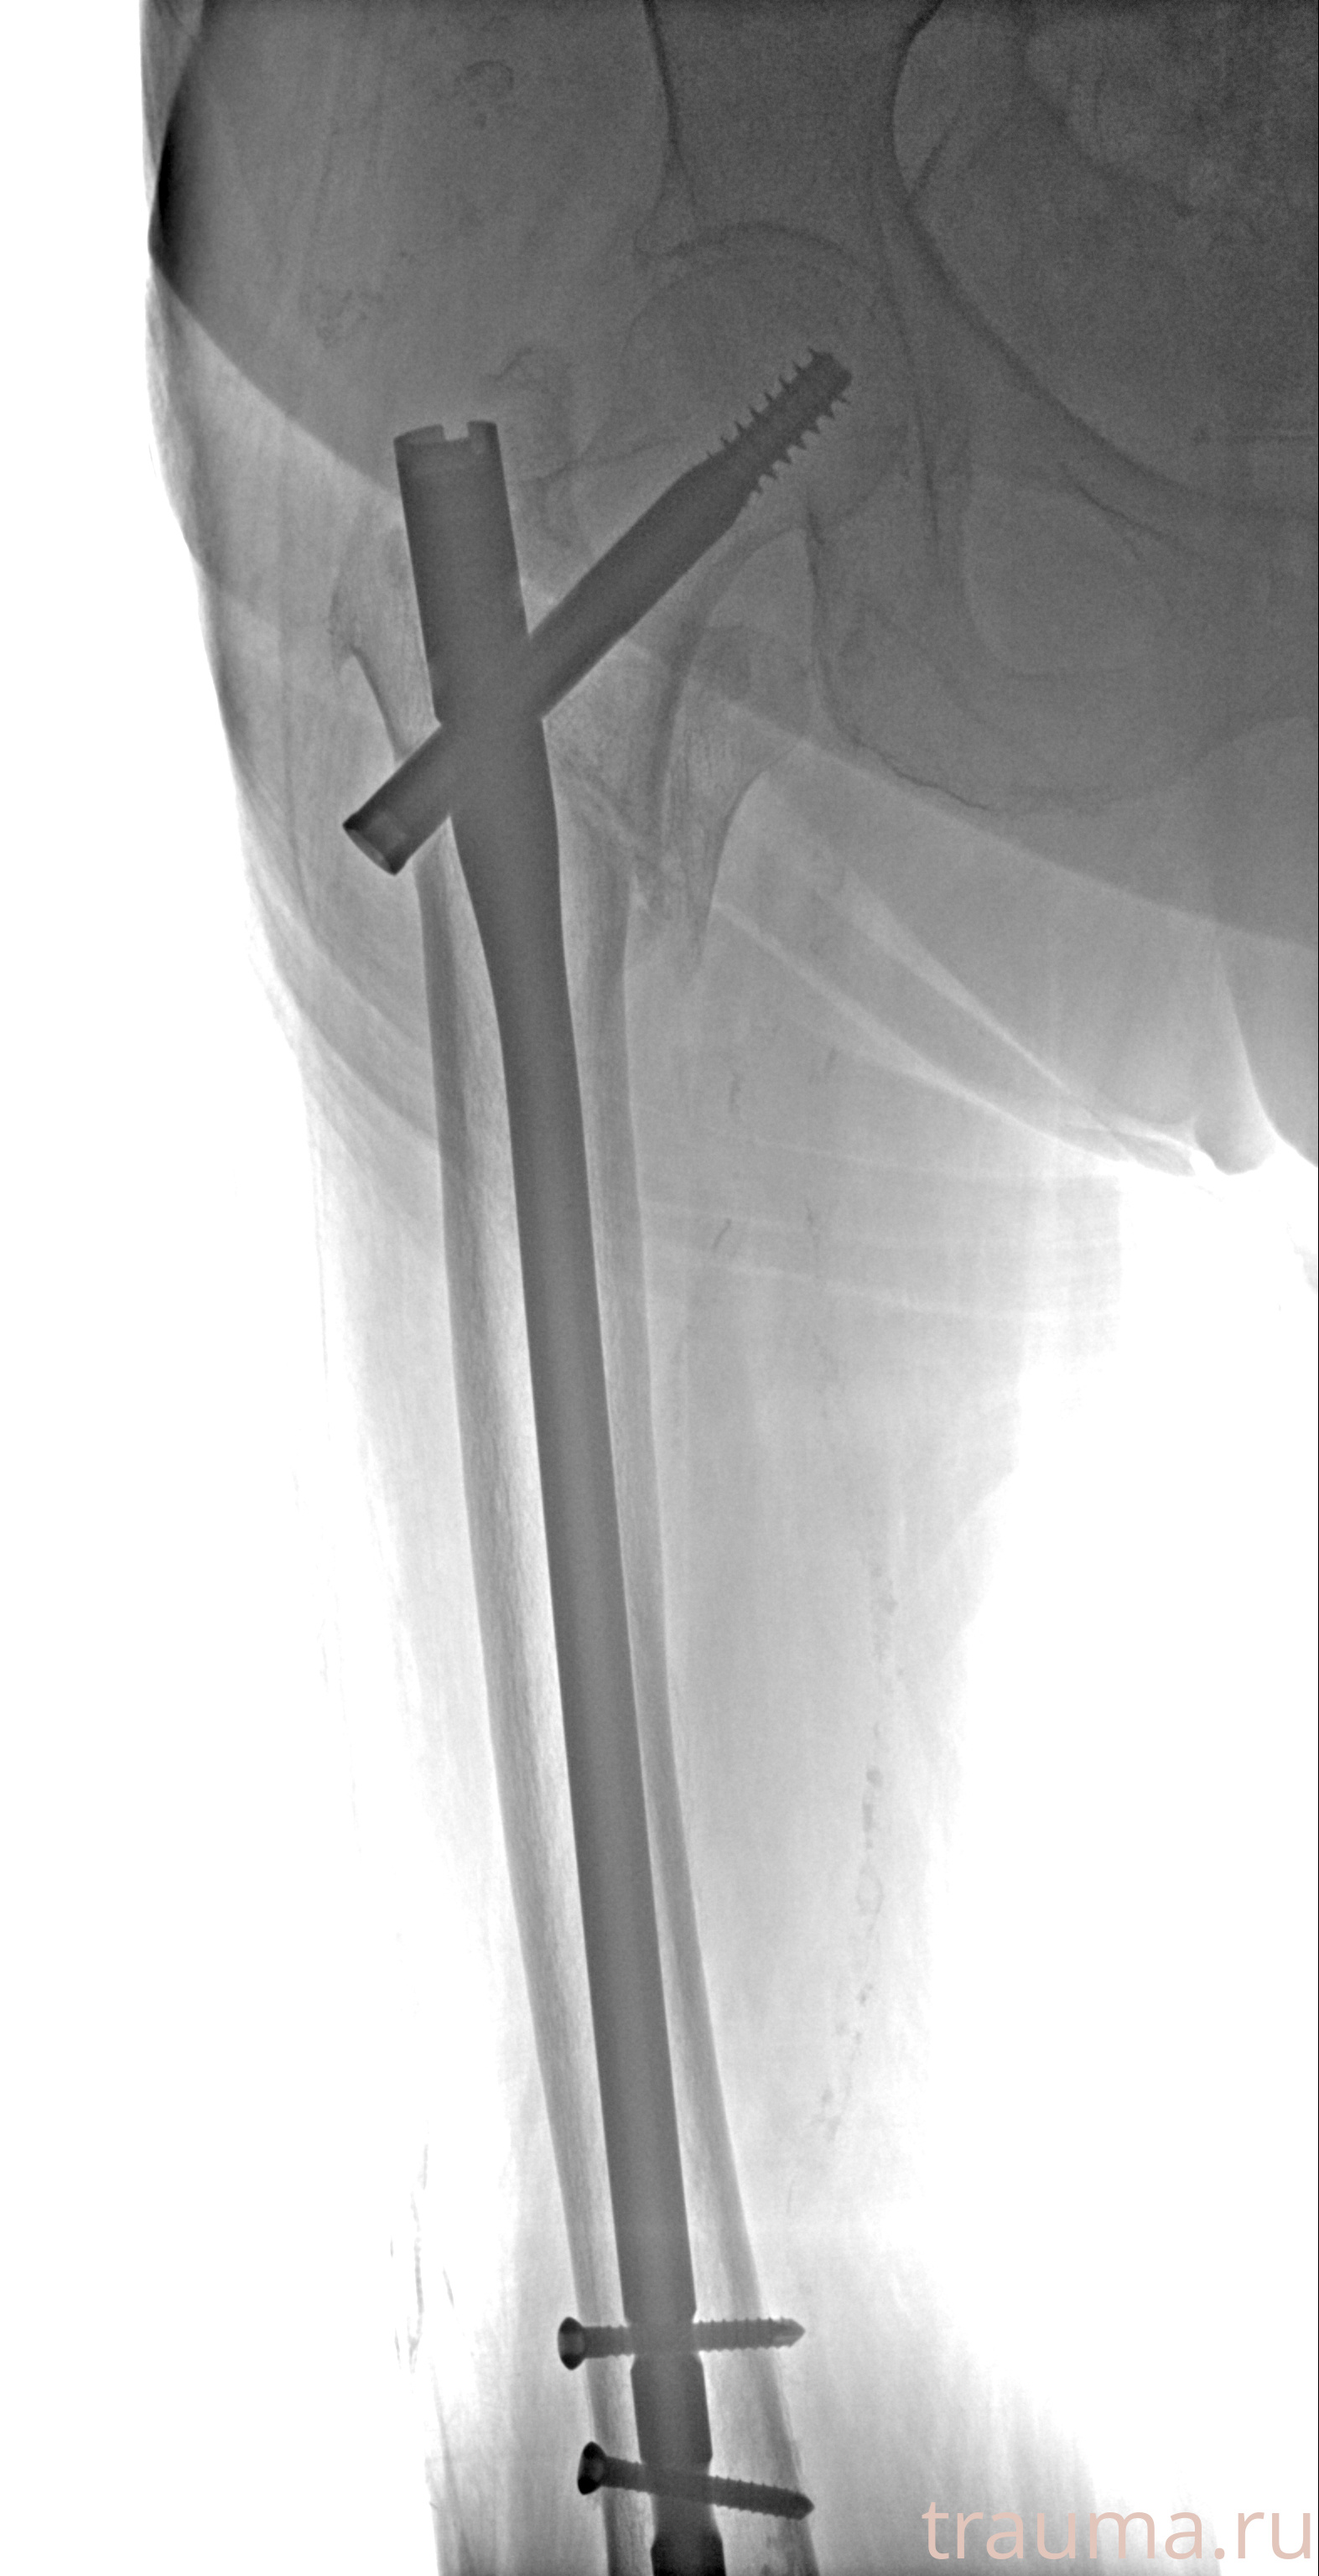

Рентгенограммы

Рентген на дому: по вашему адресу приезжает врач-рентгенолог, травматолог-ортопед с мобильным рентгеновским аппаратом, проводит диагностику травмы или заболевания, делает необходимые рентгенограммы, дает рекомендации по дальнейшему лечению. Получить качественные снимки в домашних условиях возможно благодаря уникальной методике, разработанной МосРентген Центром для института  Склифосовского